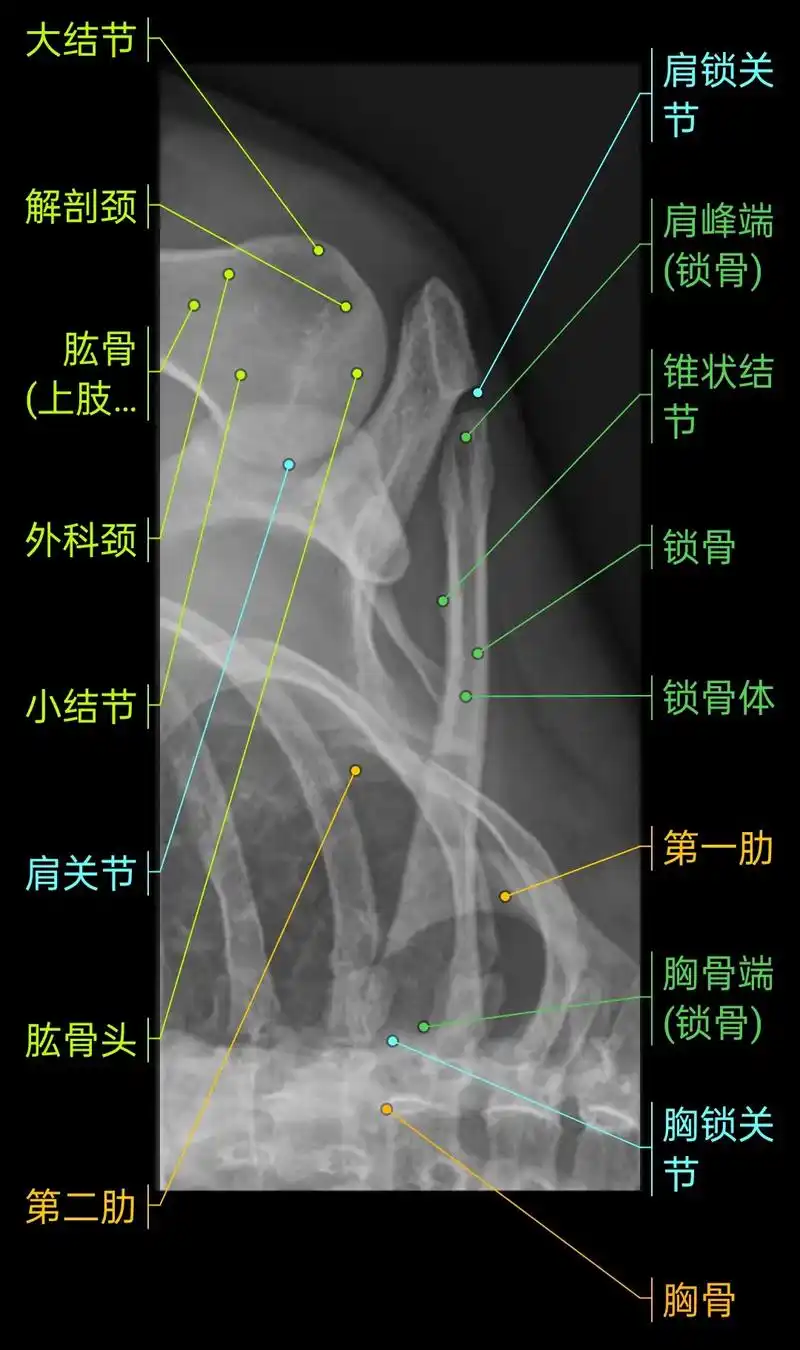

肩关节穿胸位x线图解

图片尺寸1080x810